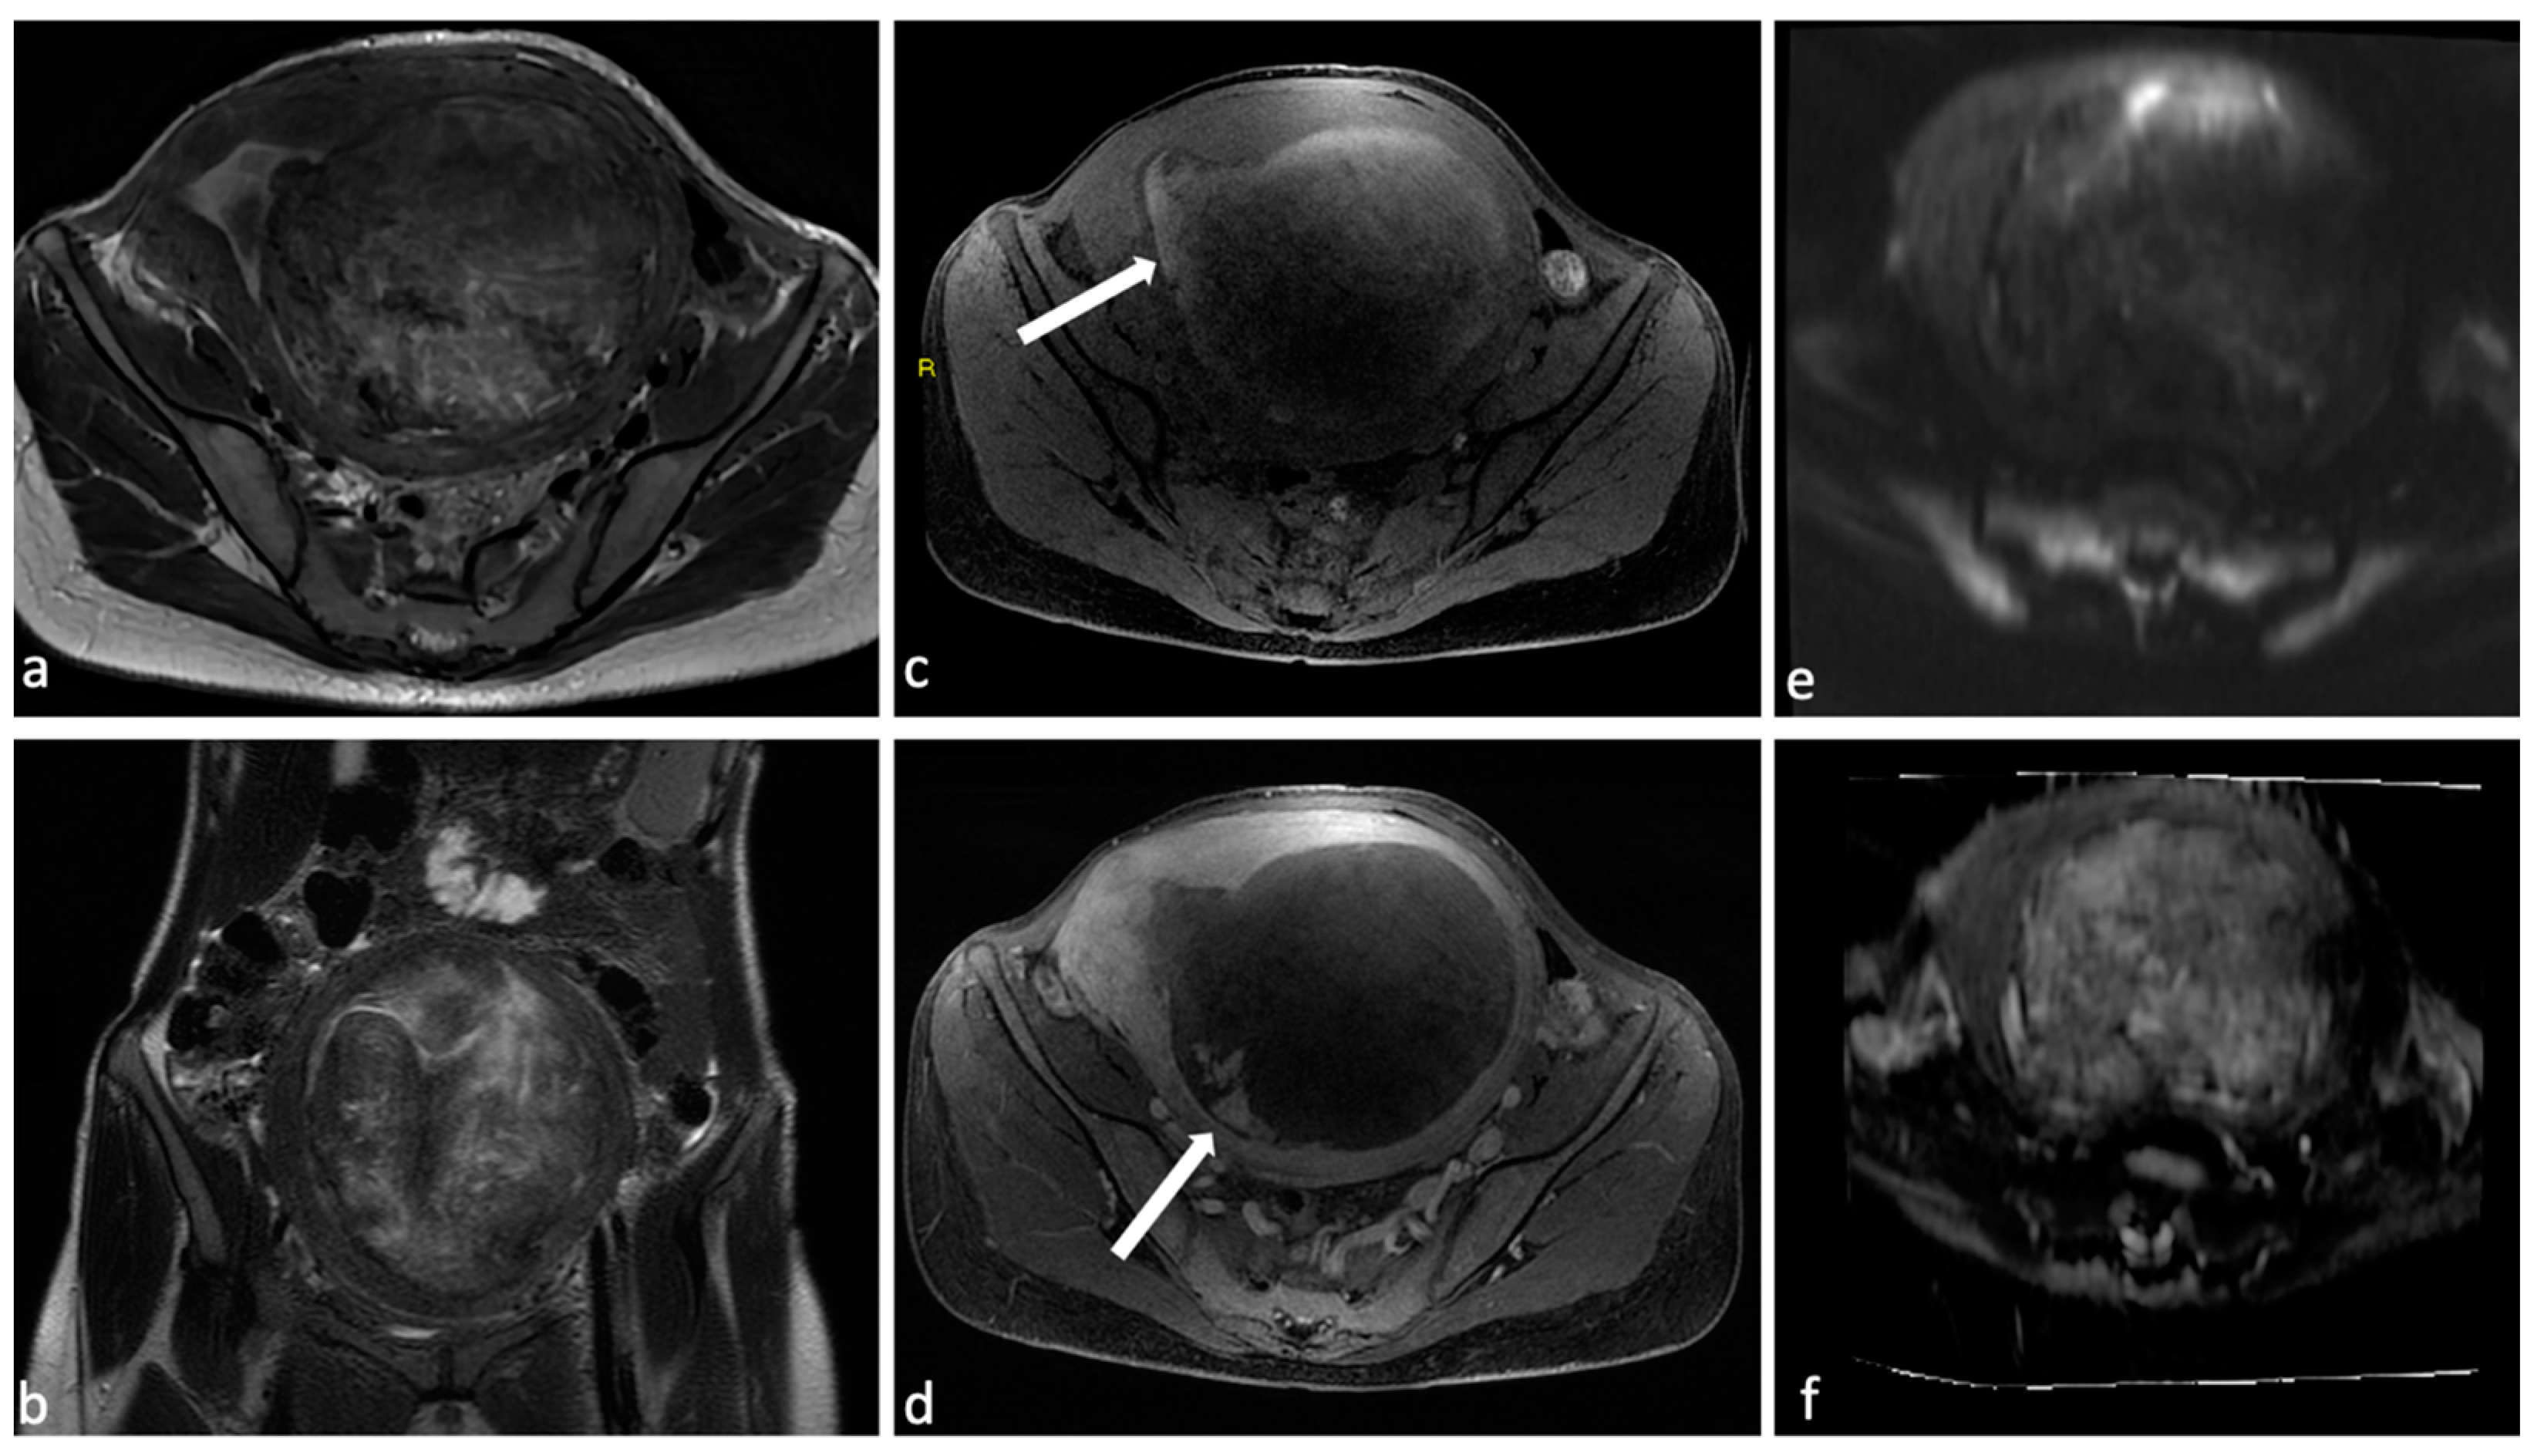

Figure 3.

Leiomyoma with red degeneration. A 43-year-old woman with known submucosal myoma with recent onset of AUB and pelvic pain. On MRI, T2 axial (a) and coronal (b) sequences show enlargement of the known submucous leiomyoma with inhomogeneous signal intensity and peripheral rim hypointensity. The leiomyoma is characterized by signal hyperintensity on T1WI (c, arrow) and a small enhancing solid portion on post-contrast T1WI (d, arrow). There is no significant restricted diffusion/hypointensity on the ADC map (e,f).